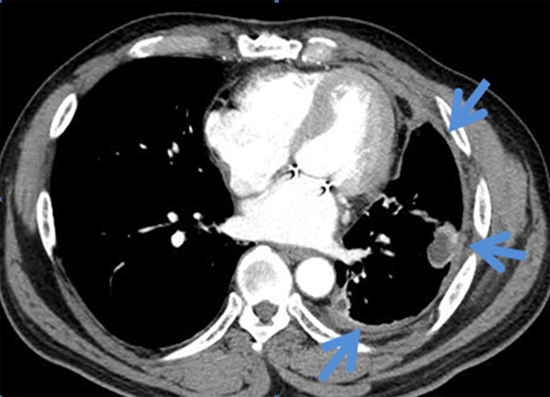

전산화단층촬영(CT)의 경우 악성중피종의 흉벽, 갈비뼈, 종격동의 구조물로의 침범 여부를 결정하는데 매우 중요합니다. 전산화단층촬영(CT) 상 정상적으로 보여야 하는 종격동 지방조직이 종양 주위에서 관찰되지 않거나 종양이 침범한 것이 확실하게 보이는 경우, 종격동 구조물의 50% 이상을 종양이 감싸고 있는 경우 등은 악성중피종이 종격동으로 침범했음을 시사하는 소견입니다.

[ 악성중피종의 전산화단층촬영 소견: 좌측폐를 싸고 있는 흉막이 두꺼워져 있는 소견입니다 ]